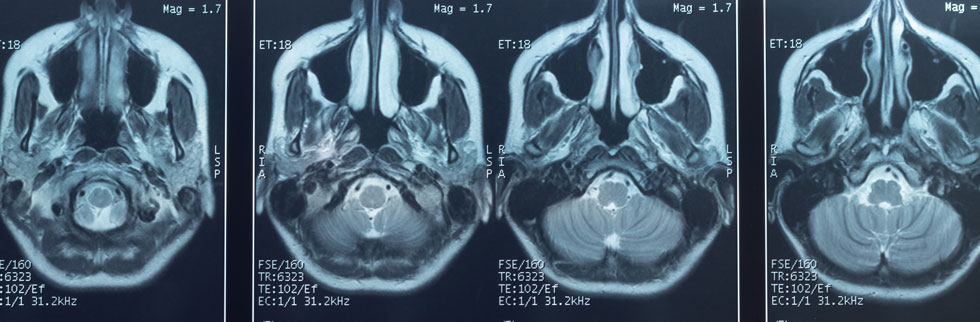

One of the most noteworthy articles to come out this past month was a Nature article comparing the brain structures of a large cohort of COVID-19 survivors before and after COVID-19. This study evaluated brain MRI scans of UK Biobank participants who were enrolled into a longitudinal multi-modal scanning study; participants were identified who had been scanned prior to having COVID-19, and re-imaged after receiving a diagnosis of COVID-19 (n=401). These participants were age, sex, and ethnically matched to uninfected controls who had had two scans with similarly elapsed time between the scans (n=384). The time interval between the two scans was an average of 3 years, and an average of 141 days from COVID-19 diagnosis in COVID-19 participants. The participants who had COVID-19 showed a greater decrease in gray matter thickness in the orbitofrontal cortex and parahippocampal gyrus when compared to controls, as well as greater decrease in overall brain volume with an additional 0.2 to 2% loss of gray matter or tissue injury between the two scans. They also displayed markers of tissue damage in areas connected to the primary olfactory cortex. Although these findings were mild to moderate overall, with some COVID-19 participants demonstrating no particular changes, these findings were statistically significant when compared to the control group. It is also worth noting that the vast majority of these COVID-19 participants were not hospitalized during their illness, with only 15 out of the 401 cases requiring hospitalization with COVID-19 (Douad 2022). There have been many reports of neurologic imaging findings in acute or post-acute COVID-19, including case reports and case series revealing such findings as white matter hyperintensities, microhemorrhages, hypoperfusion, and ischemic events in a variety of patterns, as well as rarer findings like hemorrhagic necrotizing encephalitis and ADEM (Ladopoulos 2021, Vogrig 2020, Paterson 2020). Olfactory bulb atrophy has also previously been reported, including in patients with pre-COVID imaging (Chiu 2020). There have also been a few cohort studies of neurologic imaging after COVID-19, including a PET study of 29 subacute COVID-19 patients who demonstrated FDG hypometabolism in the fronto-parietal regions (Hosp 2021). The recent Nature article by Douaud et al. is notable due to the large pre-COVID-19 imaging repository for this survivor cohort and control group, making the differences seen post-infection more likely to be related to COVID-19 (and less likely to be pre-existing).